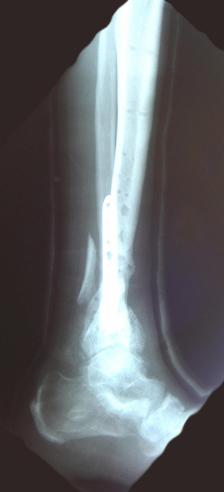

X-Rays and scans of the damaged right & left legs plus the pelvis

These x-rays were taken just after the accident. Some of the bones on the right leg have already been pushed back into the leg. The CT

scans show various views of the ankles and pelvis prior to any corrective surgery. Fibula bracing is clear in some of the images as well as

bracing that was used to secure the "open book" pelvis. In some of the last images it is apparent that the upper part of Liam’s left fibula is

broken. Liam was told that the pain he felt was most likely a muscle cramp. Nothing was done to repair this break and you will see in further

x-rays that the bone shifted and later fused in such a way as to add to the reduction of Liam’s leg length. The last photo shows the stint

used to block any potential blood clots from moving up.